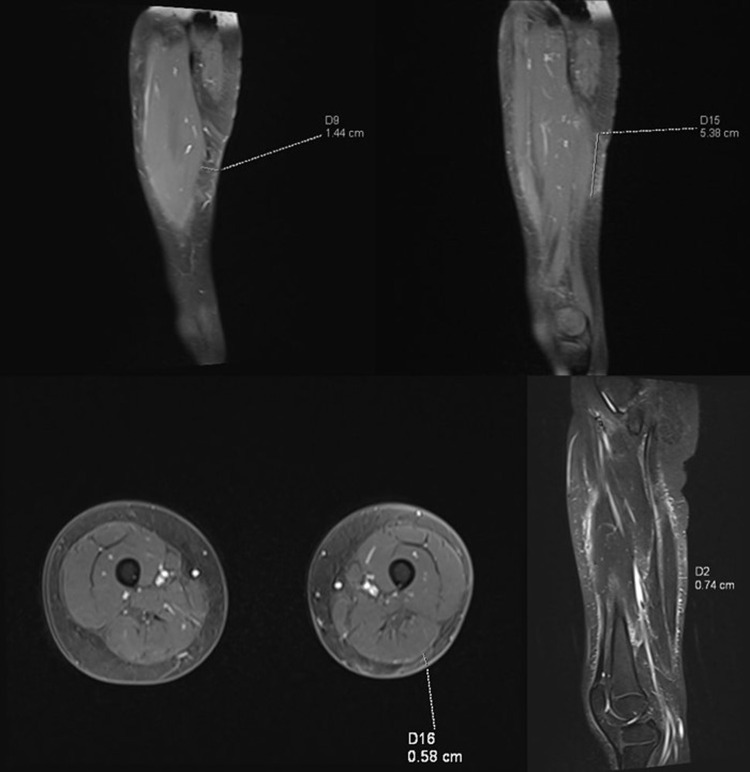

Subcutaneous panniculitis-like T-cell lymphoma (SPTCL) is a rare primary cutaneous lymphoma derived from cytotoxic αβ T cells, clinically and histopathologically resembling inflammatory diseases of adipose tissue, particularly lupus panniculitis. It accounts for <1% of all non-Hodgkin's lymphomas, with approximately 20% of cases occurring in children. The main aim of this paper was to present two pediatric cases of SPTCL, highlighting the diagnostic challenges involved. The first patient, a 5-year-9-month-old boy, was admitted with a 15 cm infiltrative lesion on the left thigh, previously misdiagnosed and unsuccessfully treated with antibiotics. Imaging revealed an infiltrate resembling lymphedema. A biopsy confirmed SPTCL with a typical immunophenotype. The patient received EURO-LB 02 protocol therapy for peripheral T-cell lymphoma, complicated by pancytopenia, respiratory infection, and polyneuropathy. Post-treatment follow-up showed lesion regression, with residual subcutaneous atrophy (5 cm). The second patient, a 7-year-old girl, presented with a 10 cm inflammatory lesion on the left thigh and systemic symptoms. Imaging and histopathology confirmed the diagnosis. She was treated with the same protocol. Three years later, disease recurrence occurred on the left forearm, managed with alemtuzumab and methotrexate. Both patients remain under outpatient follow-up. Despite its rarity, SPTCL poses a significant diagnostic challenge in children. Accurate differentiation and early diagnosis are crucial for prompt and effective treatment.